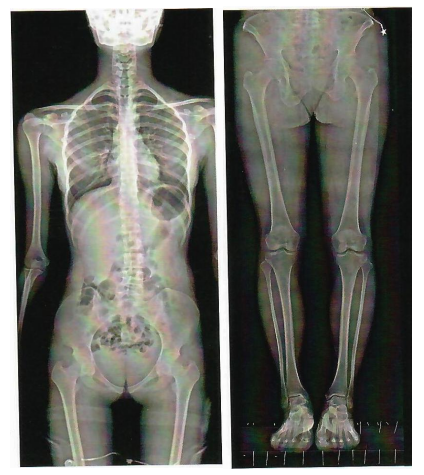

新东方摄影X射线机,开启DR“百微世界”,大尺寸平板精准成像,展现超越肉眼的丰富细节,3秒成像,超高清晰度和非凡的图像细节,十轴联动,六向跟踪,智导操控,本机具有国内最先进的智能一键自动拼接,管球无位移,消除运动误差,提高拼接成功率,重叠区域面积小,减少曝光次数,减少辐射剂量,采用AEC自动曝光和影像均衡算法,保证图像统一亮度和对比度。

脊柱侧弯和下肢负重骨骼畸形,矫正术前术后的全景摄影能直观的反映病变的程度和部位,为临床提供可靠诊断依据。